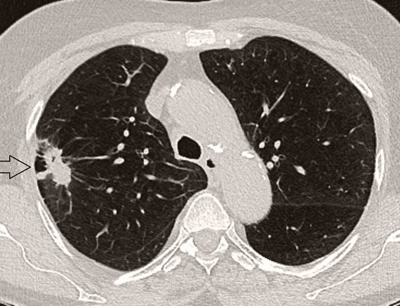

In der Radiologie Hirslanden Zürich wird das gesamte Spektrum der diagnostischen bildgebenden Verfahren angeboten.

- Hervorragende Bildqualität bei extrem kurzen Untersuchungszeiten

- Detaillierte Untersuchungsverfahren mit geringer Strahlenbelastung